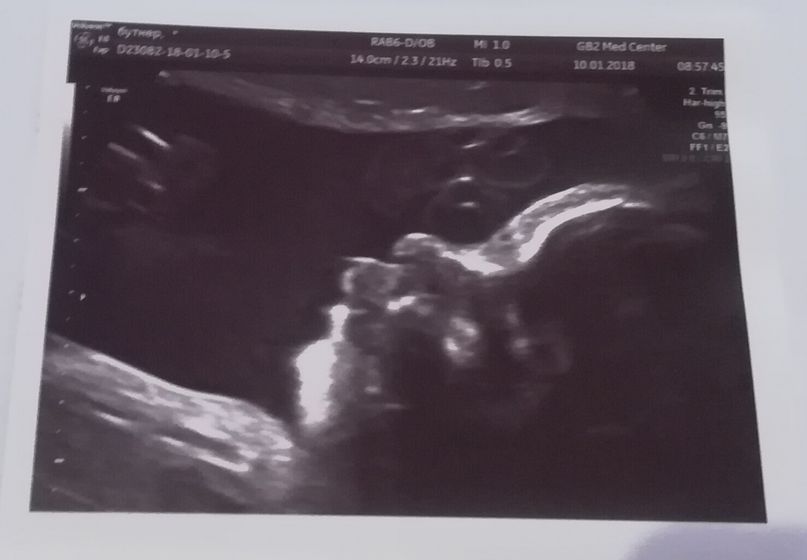

Сегодня была на 3 УЗИ. Мы правильно лежим, вниз головой. Предположили что весим 2200 гр, немного опережает срок, ой не хотелось бы в феврале, но думаю, что ни делается — к лучшему. Плацента в норме, по передней стенке и на дне матки, пишут, что нижний край плаценты нормально от области внутреннего зева. Девочку подтвердили. Единственное, обнаружили кисту у неё в яичнике, и надо идти к генетику, сказали такой порядок, а страшного в кистей ничего нет, к родам рассасывается почти полностью, а после родов пропадает совсем. Дали фото, хоть я и не просила)

Не переживайте. У нас на последнем скрининге тоже обнаружили кисту. Ездила в мдк и перенатальный. Все говорили киста аж две… родила все хорошо, отнесли ее на ренген и врач сказал какая киста!!! газики так скопились. Сделали через месяц УЗИ ничего не было. И я столько про эту кисту читала, что она рассасывается и может уже до родов исчезнуть а может и в первые месяцы

Какая классная фотка) губехи такие сладкие??? поздравляю с хорошим УЗИ.